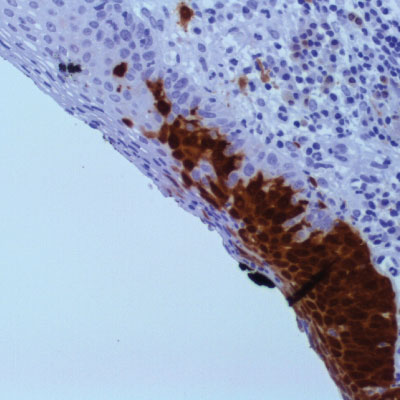

Immunohistochemistry integrates a set of methodologies that use antibodies as specific reagents capable of identifying and establishing specific links with tissue constituents that function as antigens.

Established bindings can be visualized under microscopic observation, due to the labeling of antibodies that cause color development whenever antigen-antibody complexes are formed.

​Vitro Turkey Diagnostics, through its exclusive representation of Master Diagnostica in Turkey, sells antibodies and equipment for immunohistochemical diagnosis (IHC), offering a wide panel of primary antibodies (more than 300 references), as well as universal and high-quality detection systems. sensitivity, based on micropolymer technology for in vitro diagnostics.

With the main objective of providing innovative and top quality antibodies for immunohistochemical diagnosis, we work daily to be informed of the problems and needs of the market, in order to be able to offer our customers the most innovative antibodies with total quality assurance.

Top quality antibodies for immunohistochemical diagnosis. More than 300 references.

Universal and high-quality detection systems. Sensitivity, based on micropolymer technology for in vitro diagnostics.